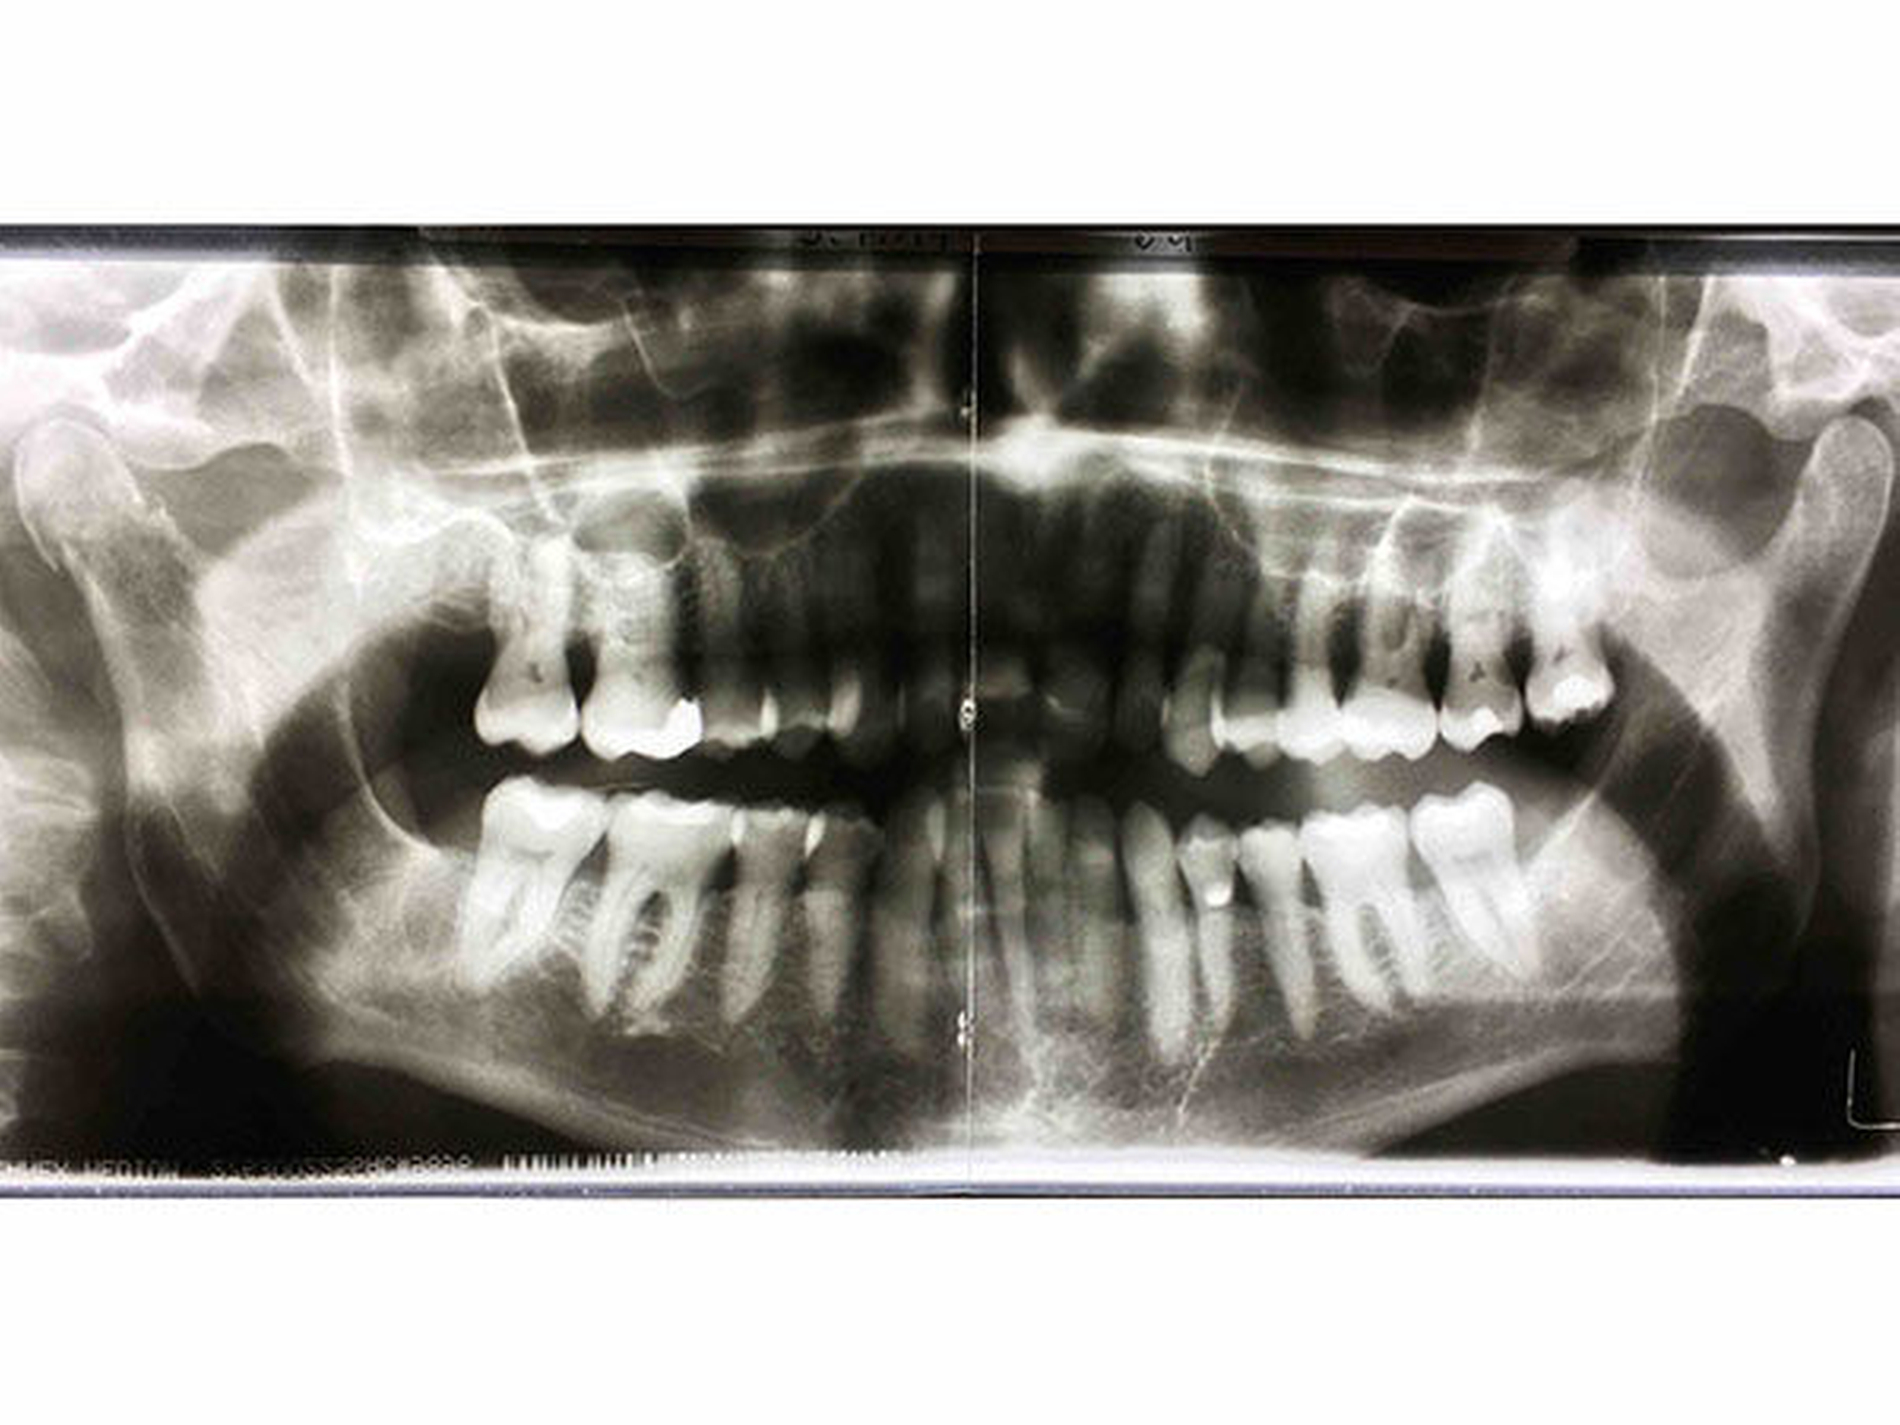

In der alio loco durchgeführten Panoramaschichtaufnahme (Abbildung 1) zeigte sich eine rechtsseitige Collumfraktur. Anamnestisch war dem Patienten kein Trauma erinnerlich.